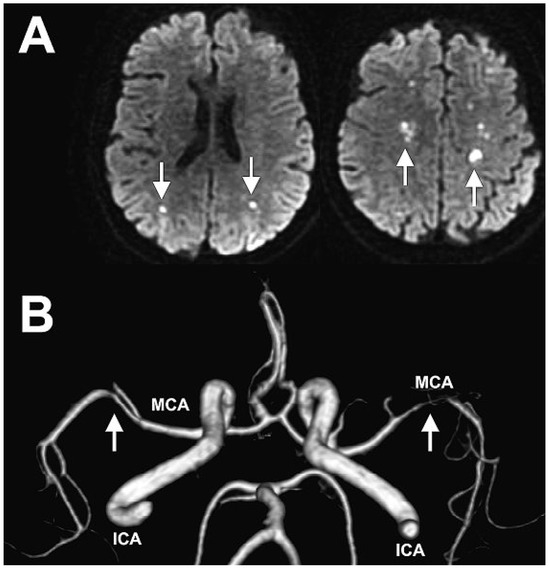

Stroke and Pulmonary Opacity

by Jean-Jacques Goy, Laurent Poncioni, Patrick Monnier, François Perret and John Wellinger

A 46-year-old woman patient was admitted for transient ischaemic attack. She was not taking medication and had no history of cardiac or vascular problems [...] Full article